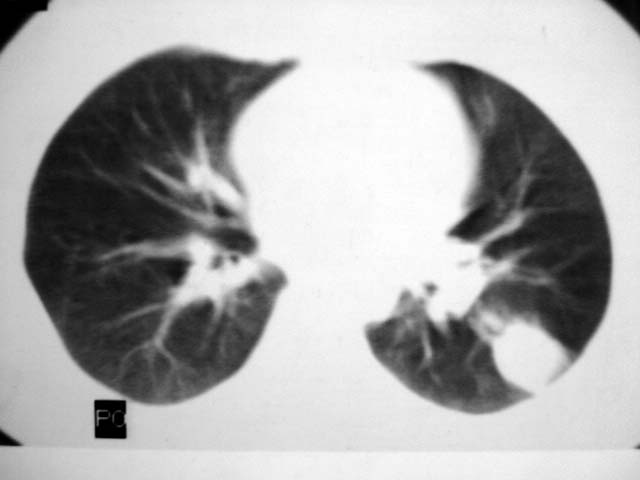

标题: CT12463:女,19岁,炎性假瘤?结核球? [打印本页]

女,19岁,体检时发现。炎性假瘤?结核球?

早产儿,幼时体弱,常感冒肺部感染,13岁后好转。两月前“感冒”后咳嗽两周。

首先要说ct机太差,片子质量不佳,一定是2秒以上机器的作品!其次ct技师需进一步培训,象这种情况就应该针对病灶部位做薄层或高分辨扫描。不过从上传影像看,患者年轻、病灶周围没卫星灶倒支持炎性假瘤诊断,不过象这种部位也有可能是叶间包裹性积液可能。只是ct机太、太差,很难诊断,如一秒机扫描出来90%可直接诊断,有必要时可结合矢状位三维重建。所以要我说建议患者在亚秒(至少是1秒)机上重扫十分有利于正确诊断。

考虑炎症,抗炎后复查。理由:病变肺窗显示的大小明显大于纵隔窗,提示病变周围为密度偏低的渗出改变。不同于结核球和肿瘤。